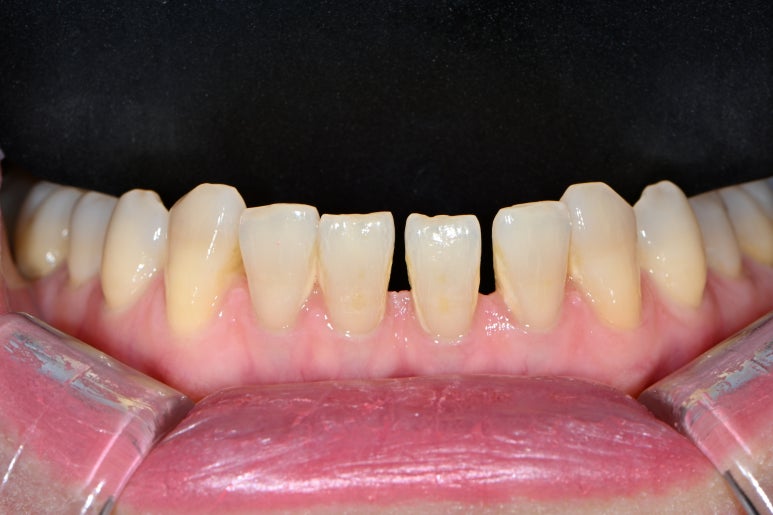

앞니 레진치료를 오랫동안 받아왔는데, 변색 때문에 괴로워요..

앞니 벌어짐도 해결하고 싶어요.

앞니 벌어짐과 앞니 레진 변색을 해결하고 싶은 마음에 압구정 치과에 방문하신 환자분입니다.

잘 보시면, 떼워놓은 앞니 레진 경계가 변색이 되서 갈색으로 보이시는 걸 확인하실 수 있죠??

파란색 빗금친 부위가 대략적으로 레진이 붙어있는 부위입니다.

물론 이만큼 레진으로 치료해내는 것부터 정말 고수이셨을 겁니다.

그렇지만, 시간이 지남에 따라 생기는 레진 변색은 거의 필연적이죠... 결국은 재치료 또 재치료....

빨간색으로 표시된 부위는 가운데 앞니의 빈틈을 메우기 위해 레진을 치아 옆에 붙여놓은 곳입니다.

그래도 요기는 변색은 없네요! 다만 색상의 부조화가 조금 있네요 ^^;;

위 치아만 보면 변색이 더욱 도드라집니다. 치아가 얼룩덜룩하죠.?

씹는 면에서 보시면 더욱 문제점이 잘 보입니다.

앞니 사이에 공간도 많으시고... 기존의 레진은 하염없이 두껍게만 붙여나가고 있는 수순이고..

앞니 벌어짐 + 레진 변색은 정말로 라미네이트 치료를 받기에 가장 적합한 경우라고 생각합니다.

그리고 하나 더 ! 이 분의 경우 아래 앞니에도 치아 사이 공간이 있어 많이 벌어짐이 있었는데요,

옛날부터 어르신들이 치아가 벌어져 있으면 복이 새어나간다고 하시잖아요~ 레진으로 양 옆에 붙여서 메꿔주는 것도 방법이지만, 얇은 세라믹을 붙여서 앞으로 변색 없이 완벽한 모양과 색상으로 유지해나가실 수 있을겁니다.

아래 앞니도 교합면에서 보면 생각보다 치아 사이 벌어짐이 많이 있으신 것을 보실 수 있을겁니다.